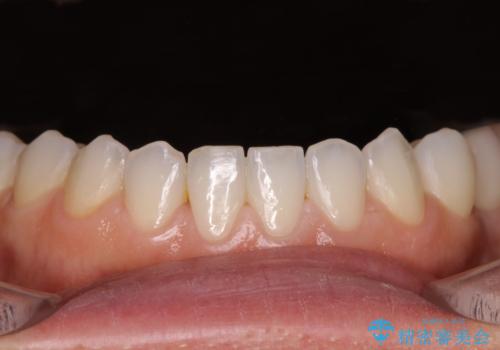

- 大きすぎる上顎前歯と、隙間の空いた下顎歯列を気にして来院された患者様です。

下顎前歯は空隙歯列弓であったので、アンカースクリューとワイヤー装置を用いてスペースを閉じていくこととし、上顎前歯は矯正治療用の仮歯に置き換えた上で、仮歯の大きさを削って小さくしながら、上下前歯部の部分矯正を行うこととしました。

矯正治療後は、仮歯とした上顎前歯をオールセラミッククラウンにて補綴治療を行うこととしました。

日本と海外を拠点に仕事をされていらっしゃるため、数ヶ月治療があいてしまうことがあり、期間はかかりましたが、2年間で望み通りの前歯に仕上げることができました。